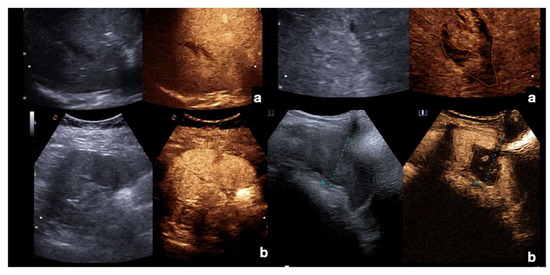

Admission CT (a,b) and follow-up CEUS (c–o) of a 35−year-old blunt trauma patient with multiple hepatic lacerations. Follow-up CEUS was performed 3 days (c–e), 11 days (f–i), and 20 days (l–o) after the admission CT. Note at CEUS the progressive enhancement of the liver parenchyma in the different phases. The parenchymal lacerations appear as non-enhancing bands (c, orange line), some of them reaching the liver capsule (pink line) (e,i). In the follow-up, it is important to look for possible vascular injuries (absent in this case) in the early arterial phase (f,l). Parenchymal lacerations appear progressively better demarcated, and more hypoechoic. Adopted from ref. [30], 2021, Iacobellis, F.; et al.

Figure 15.

Admission CT (a,c,e) and follow-up CEUS (b,d,f) of the spleen in a 35−year-old patient after a fall from height. Follow-up CEUS was performed seven days after the CT. Note at CEUS the progressive enhancement, at different time points, of the healthy spleen parenchyma in venous phase, clearly demarcated from the subcapsular hematomas (b, orange line), from the contusion of the inferior-pole (d, orange line) and from a sub-capsular laceration (f, orange line). Adopted from ref. [30], 2021, Iacobellis, F.; et al.